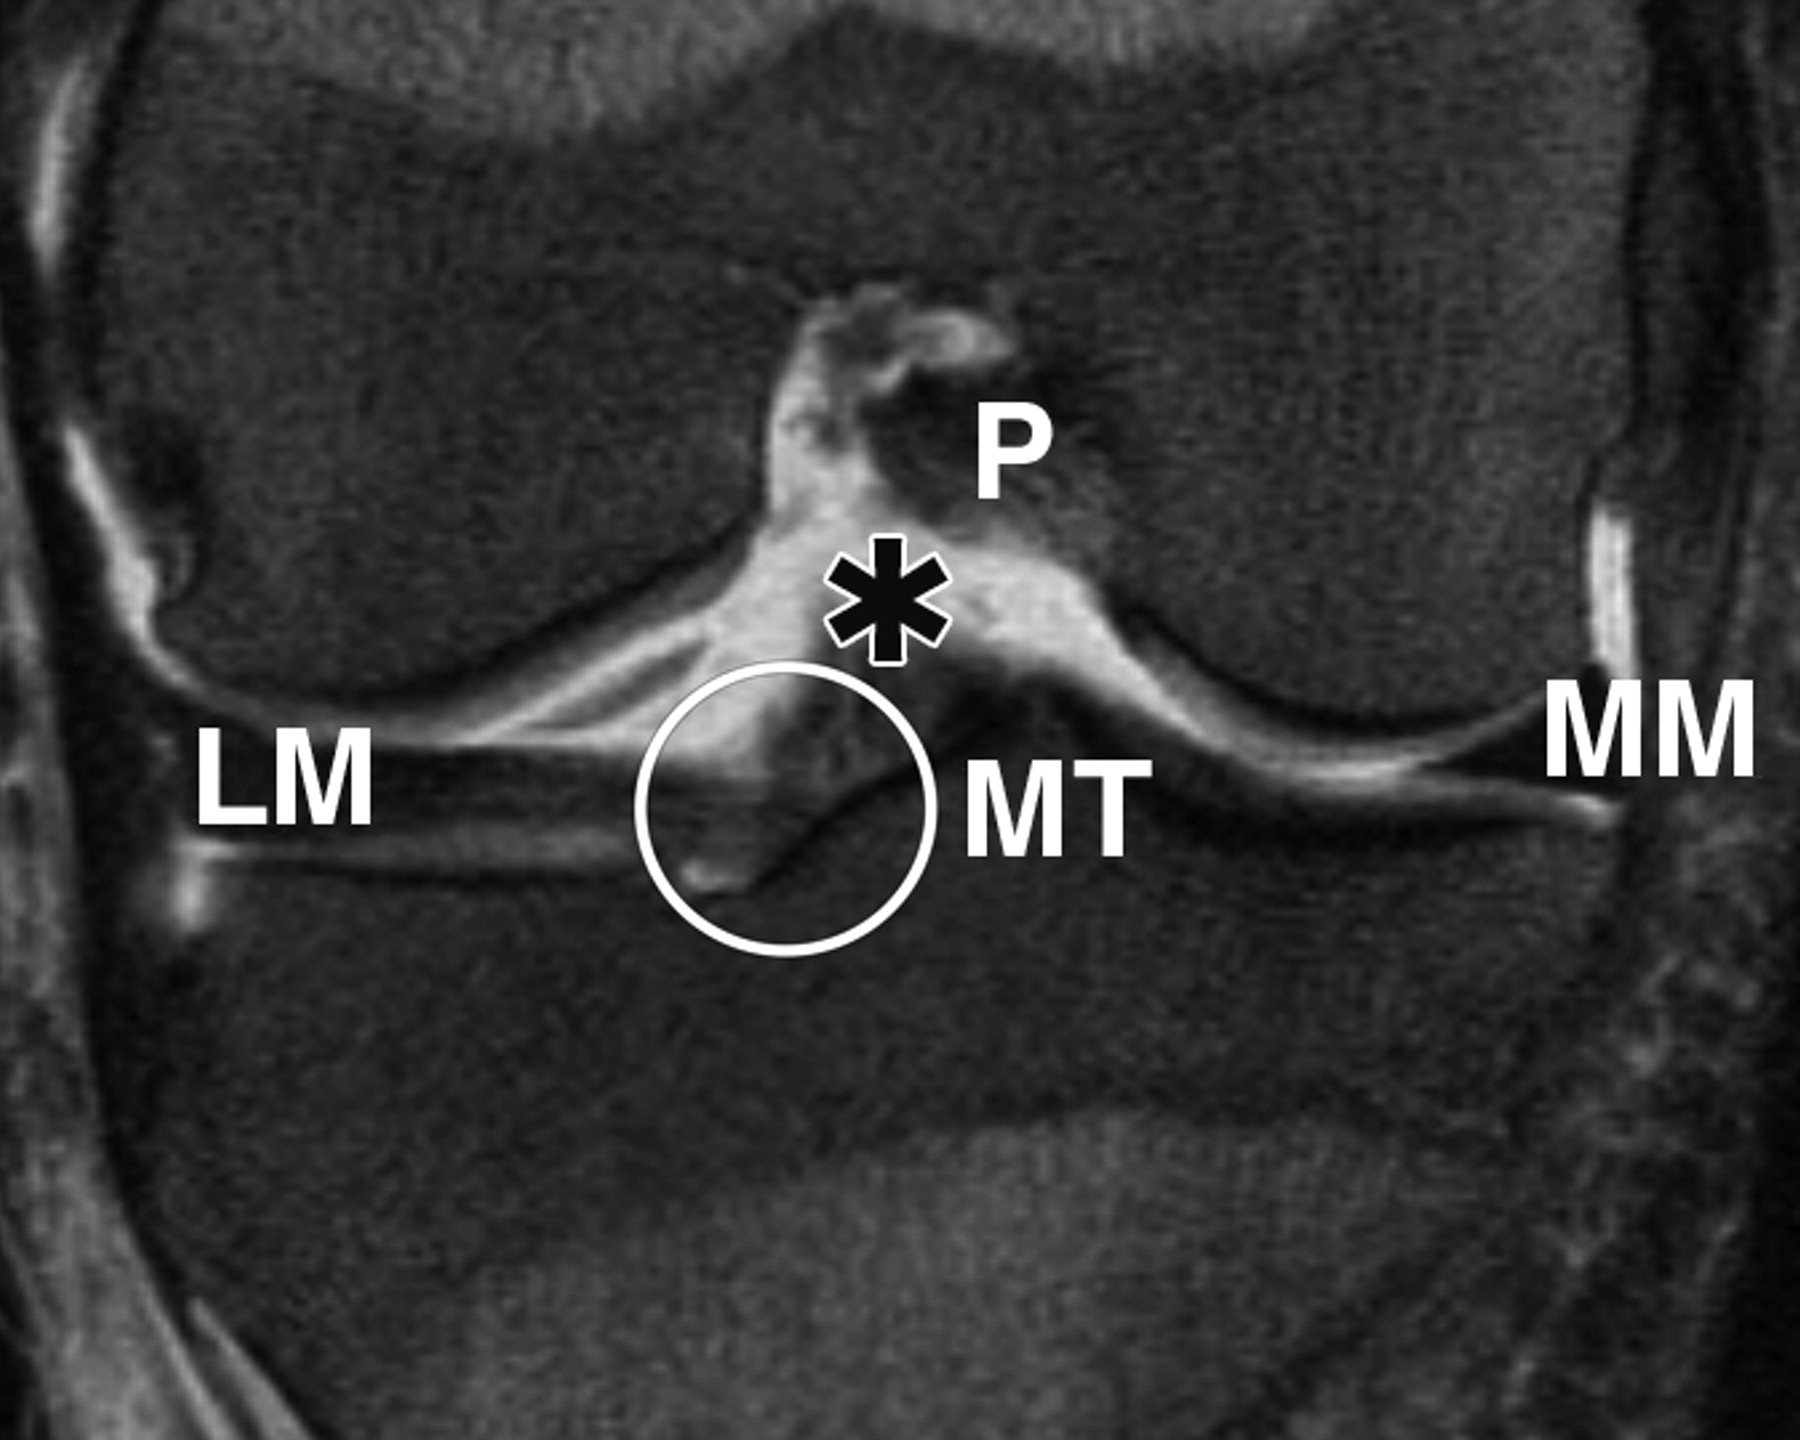

图3B-51岁女性。

膝关节的中等加权、脂肪饱和、快速自旋回波(TR/TEeff,3,700/29)3-T MR图像显示了膝关节前根、前交叉韧带(ACL)和膝横韧带的解剖关系。相对于A的后部冠状位MR图像显示内侧胫骨结节(MT)外侧斜面上外侧半月板(LM)前根的附着点(圆圈)接近ACL胫骨附着点(星号)。P =后交叉韧带,MM =内侧半月板。